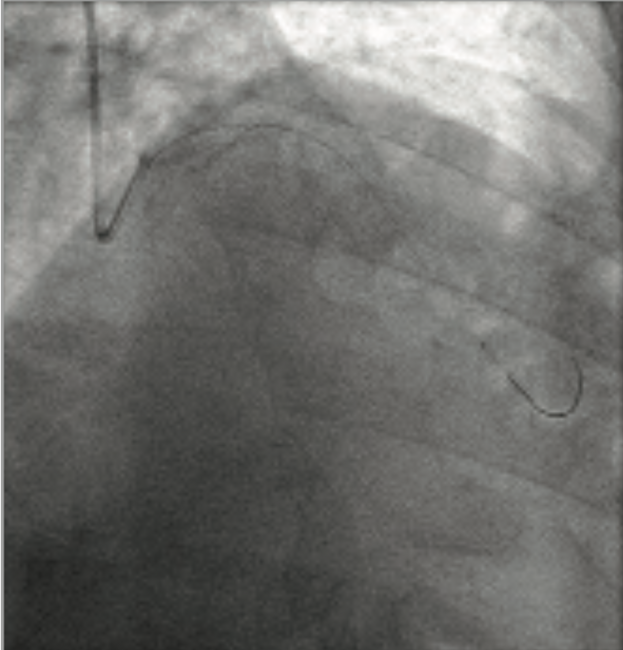

Transradial Bifurcation Stenting With Physiologic Guidance

Transradial percutaneous coronary intervention (PCI) can accommodate the vast majority of procedures using a 6 French catheter system. In this case, we describe a transradial bifurcation stenting procedure guided by physiology.

A 71-year-old man with angina was able to achieve 8.2 metabolic equivalent of task (METs) on a treadmill-ECG stress test, but developed ST-segment depression and angina with exertion. In the catheterization lab, he had right radial access with a single double-wall puncture attempt with ultrasound guidance. The ultrasound confirmed an adequate radial artery size to accommodate a 6 French (Fr) GLIDESHEATH SLENDER® Introducer Sheath (5F outer diameter), which was inserted over an .025-inch plastic hydrophilic guidewire. There was no difficulty in advancement due to the hydrophilic coating on the sheath.